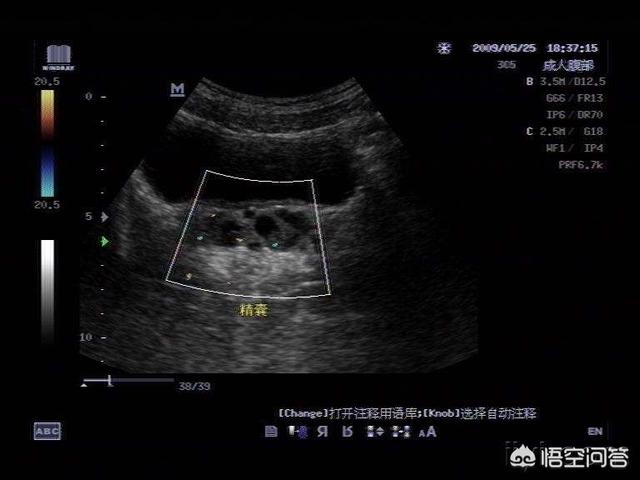

看看精囊腺与前列腺的解剖关系——

两者的炎症不仅在感染途径和病因方面相同,临床表现也差不多。由于前列腺与精囊均开口于后尿道,是邻居关系,精囊炎常与前列腺炎同时发生。

精囊炎的诊断——

血精等临床表现、精液检验结果、彩超和核磁共振可以明确诊断。